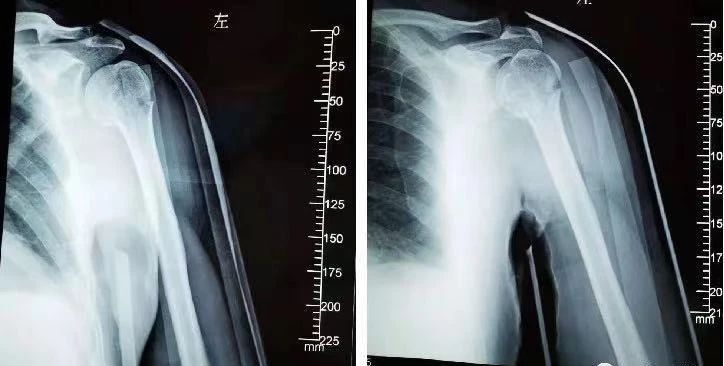

(4)肱骨外科颈骨折

肱骨大结节骨折:肩外侧大结节处压痛,外展活动受限,上臂内侧无瘀斑,无环形压痛。

肩部挫伤:系直接暴力所致,局部皮肤有擦伤、瘀斑,肿胀、压痛局限于着力部位,无环形压痛及纵向叩击痛;X线片无骨折征象。

肱骨外科颈骨折:肿痛在肩部,肱骨上端压痛;X线正位片及穿胸位可显示骨折线在肱骨解剖颈下2一3cm;治疗后骨折多能愈合。